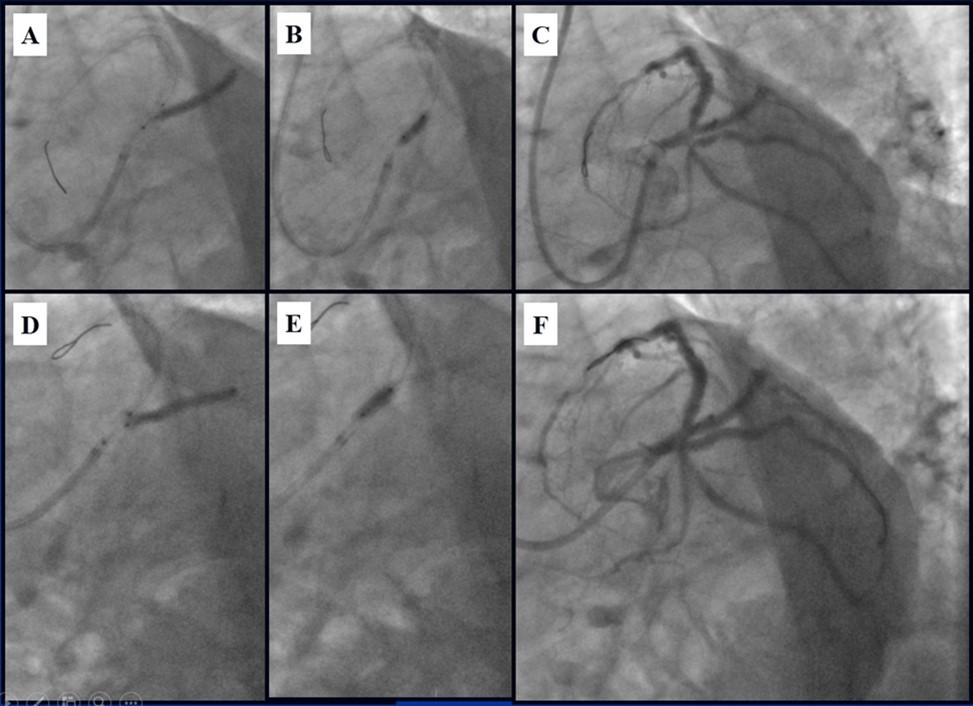

In the first stage, despite the fact that BMS is contraindicated in diabetic patients, RCA was stented with 3 bare-metal stents (BMS) (Rebel, Boston Scientific) (due to financial problems - drug-eluting stents was not covered by insurance). We used BMS to have at least temporarily patent RCA during LMCA stenting (Figure 5) (we believe that, when RCA is functional, LMCA stenting is safer). LAD was stented with 2 drug-eluting stents (Resolute Integrity, Medtronic). After the first PCI patient’s symptoms were relieved (Figure 6).

Figure 5.A, B, C - Stenting of the RCA with BMS; D - Angiography result.

Figure 6.A, B - Stenting of the LAD with DES; C - Angiography result.

Due to financial problems the second stage was performed after 3 months (during this time the patient solved his financial problems). CAG revealed patent stents in LAD (Figure 7), and 60-70% restenosis by BMS in RCA (Figure 8). In-stent restenosis was treated by plain old balloon angioplasty (POBA), the optimal result was obtained (Figure 9). After LMCA quadrifurcation balloon predilation, 2.5×26 mm DES (Resolute Integrity, Medtronic) was implanted in the IMA, using a modified balloon mini-crush technique. The stent was minimally protruded in the LMCA and its edge was crushed by preloaded MB balloon. Next 2.5×30 mm DES (Resolute Integrity, Medtronic) was implanted in OM1 through the CX (first marginal and circumflex arteries in this particular case have the same ostium). The stent was protruded in the LMCA as in conventional modified balloon crush stenting technique, after stent deployment, its balloon was pulled back and overinflated, then protruded stent was crushed by preloaded MB balloon (Figure 10). 3.5×15 mm DES was implanted in the LMCA so that distal part of the stent covered ostial and proximal segments of the LAD. Sequential post-dilatations were performed using a kissing balloon technique (1. LMCA-LAD-IMA,2. LMCA-LAD-CX-1OM). After post-dilatations, through the stent implanted in CX-OM1, coronary wire and smaller diameter balloon (2.0 mm) were advanced in direction of the CX mid-segment and by balloon dilatation stent’s strut was opened (provisional stenting technique for CX). Finally, the proximal optimization technique was performed in the LMCA using a 3.5 mm diameter non-compliant balloon (Figure 11). The final angiographic image was good, the intervention ended without complications (Figure 11, Figure 12). We could not confirm the result with IVUS or OCT due to several technical and financial problems (not covered by insurance). 1 month after PCI, at regular checkout, the ejection fraction was 48%, the functional class of the Congestive Heart Failure decreased from class II-III to class I and the patient complaints have been disappeared.

Figure 10.Stenting of the LMCA quadrifurcation: A, B - balloon modified mini crush stenting of the IMA, C - angiography result, D,E - modified balloon crush stenting of the CX-OM1, F - angiography result.